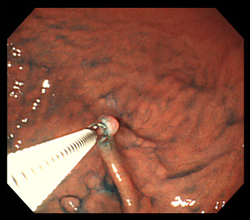

위 내시경 중 시야를 확보하면서 의심 부위를 찾으면, 내시경 기구 끝에 있는 ‘겸자’를 이용해 조직을 2~4조각 정도 채취합니다. 병변이 넓거나 불균일할 경우, 여러 위치에서 추가로 채취합니다.

- 궤양: 변연부 중심

- 용종: 꼭대기와 주변부

- 화생성 위염: 전정부와 체부를 나눠 채취

- 바렛식도: 2cm마다 4방향으로 균등 채취